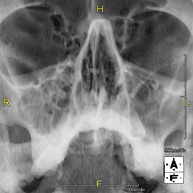

Técnica mediante la cual, utilizando rayos X, se obtienen imágenes del cráneo para su estudio. Indicaciones: traumatismo, cierre precoz de suturas craneales. - RX Senos Paranasales

Técnica mediante la cual, utilizando rayos X, se obtienen imágenes de los senos paranasales para su estudio. Indicaciones: dificultad respiratoria nasal, tos crónica, cefalea, mucosidad. - RX ATM (Articulación Temporo-Mandibular)